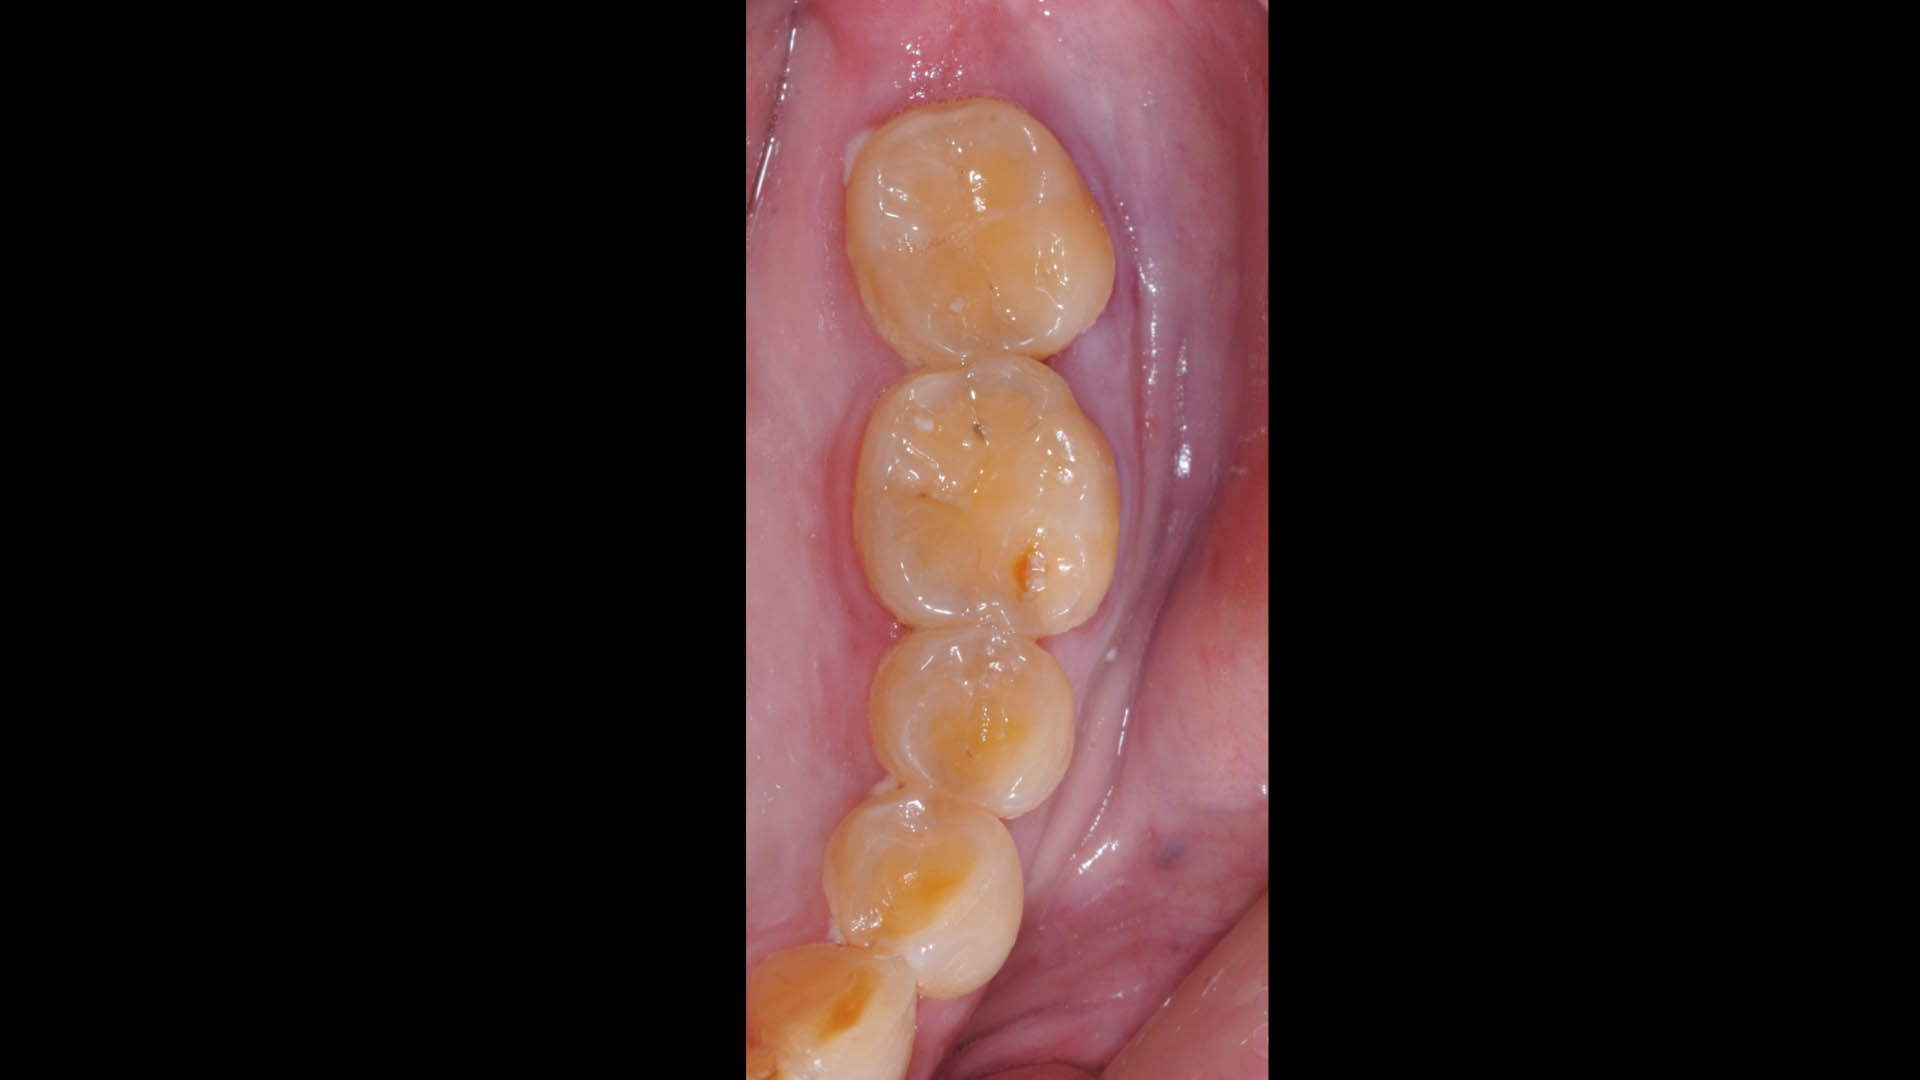

Take a glimpse into the magic of Coral Gables Dentistry through our before and after pictures. See firsthand the incredible smile makeover transformations that have brought confidence and joy to our patients.